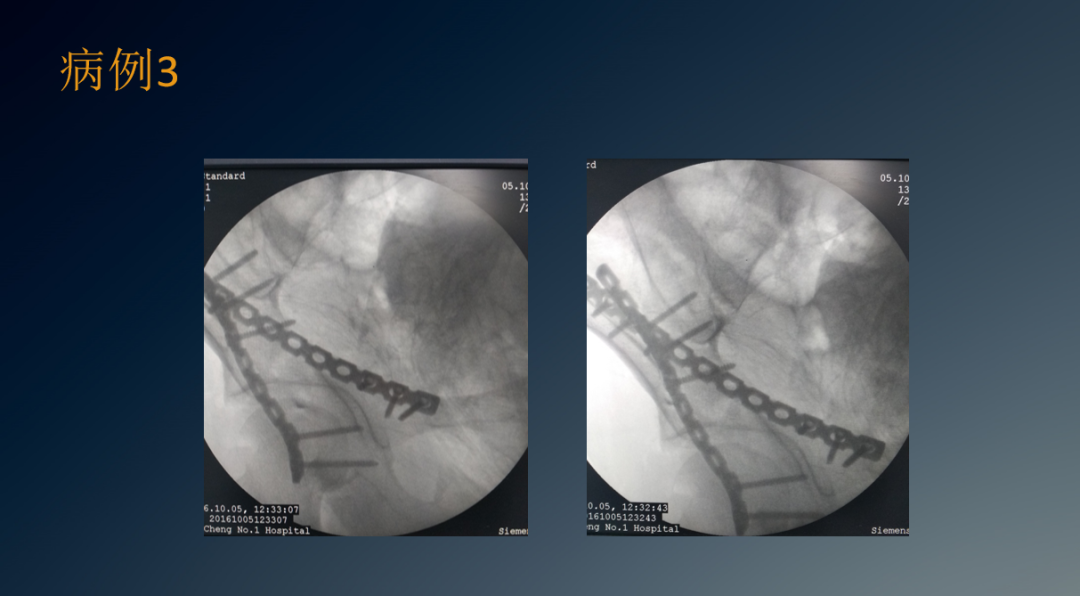

临床病例